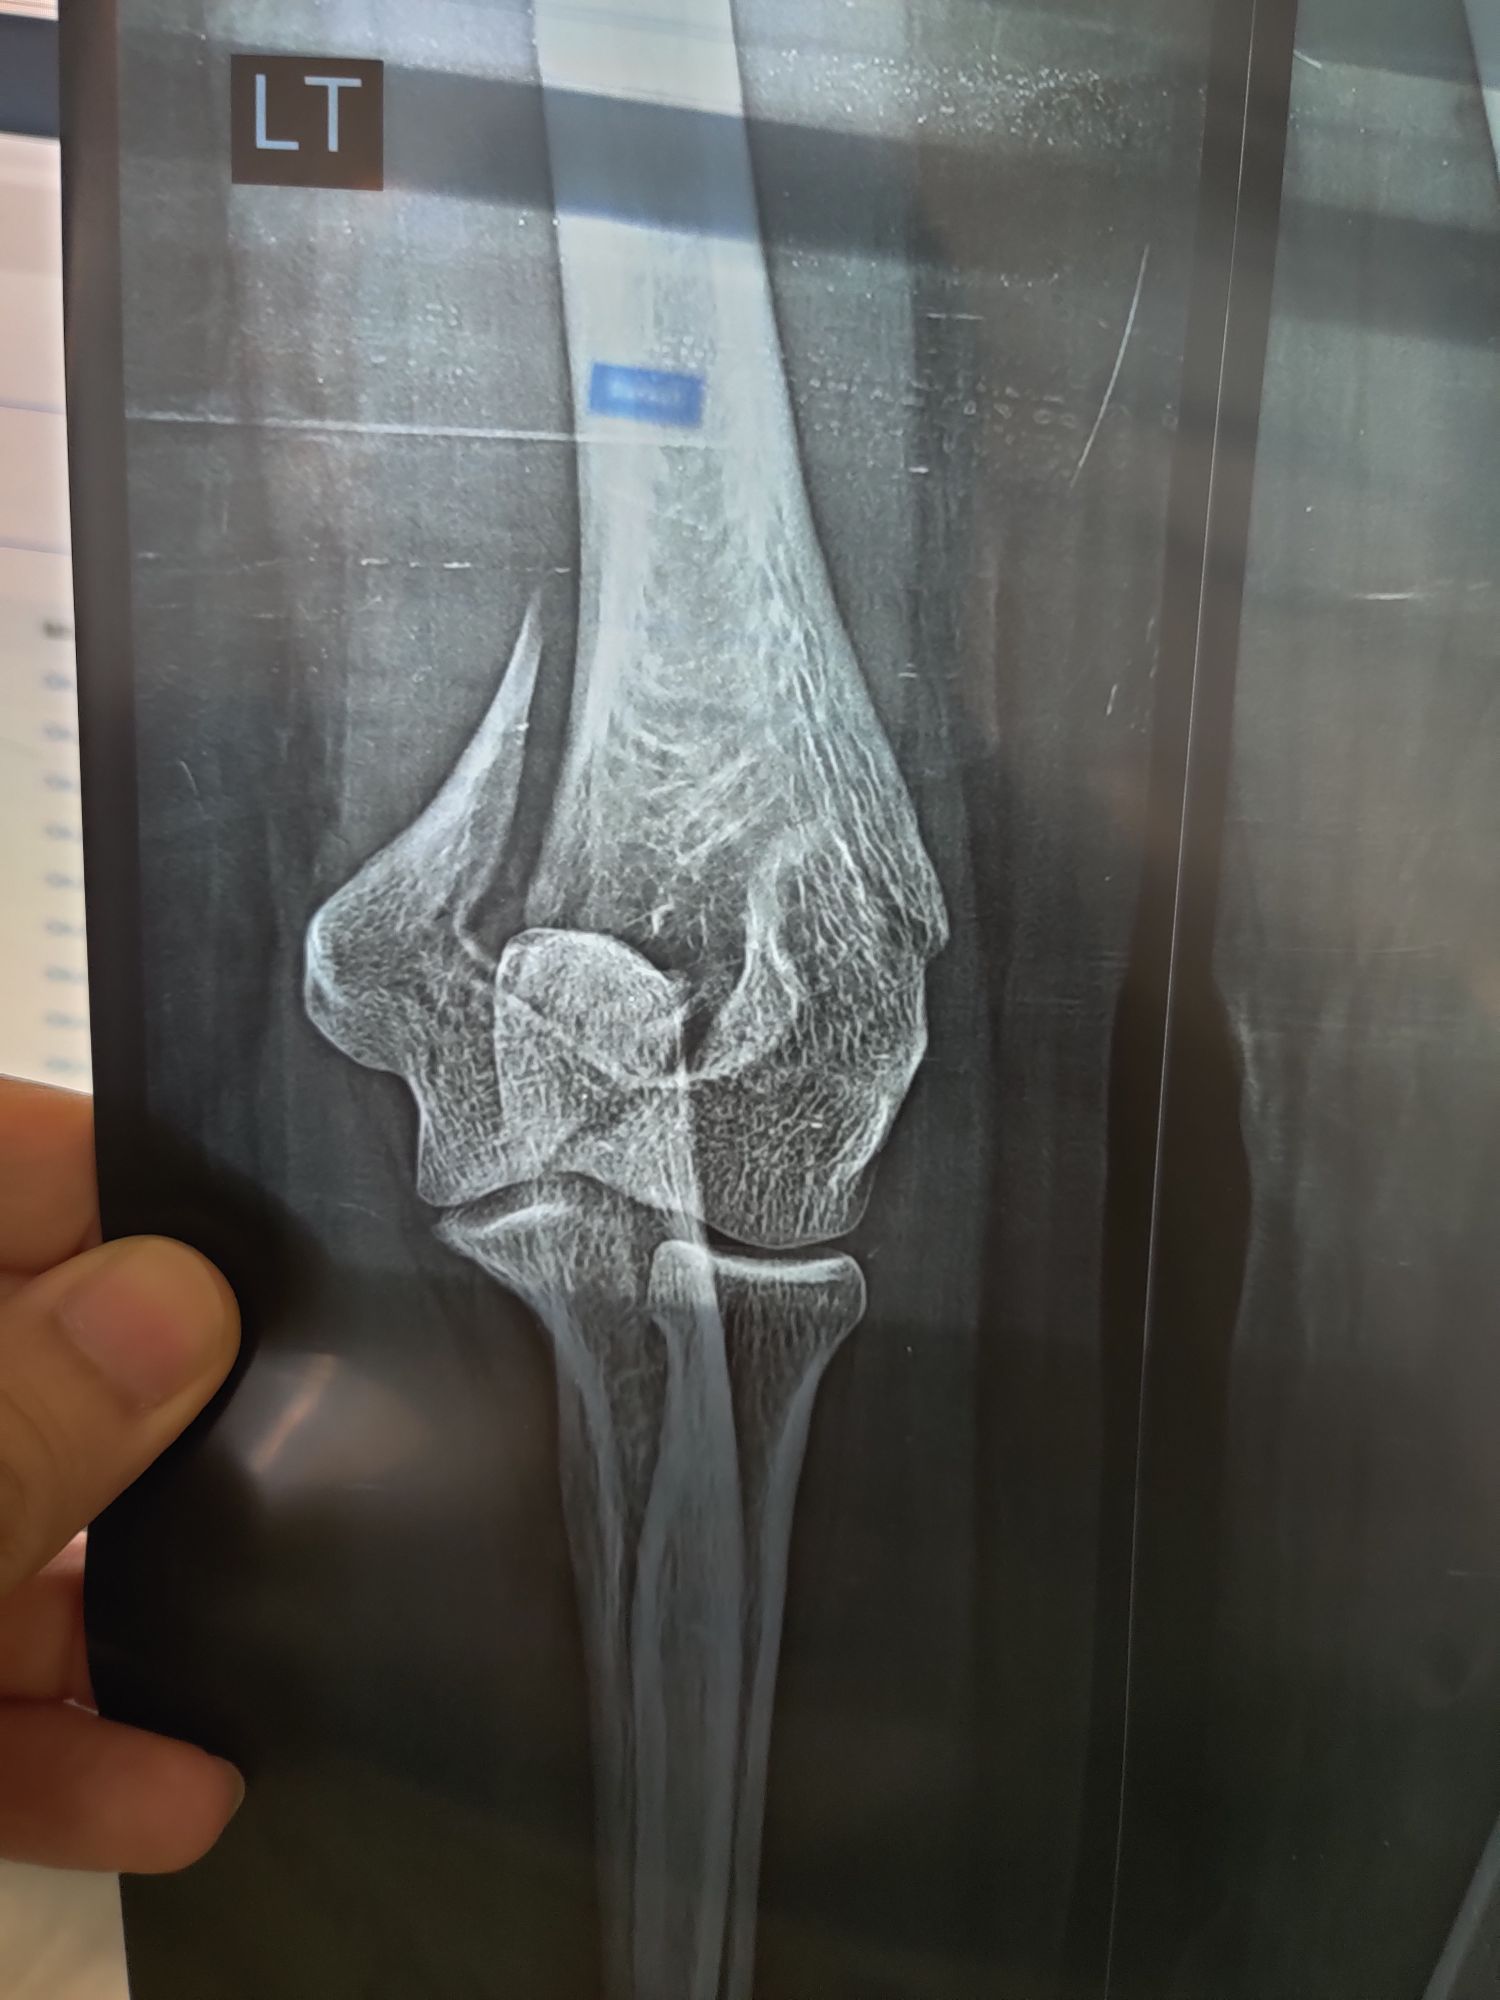

Dr Usman

Fx Humerus

Fracture

Ortho

Humerus